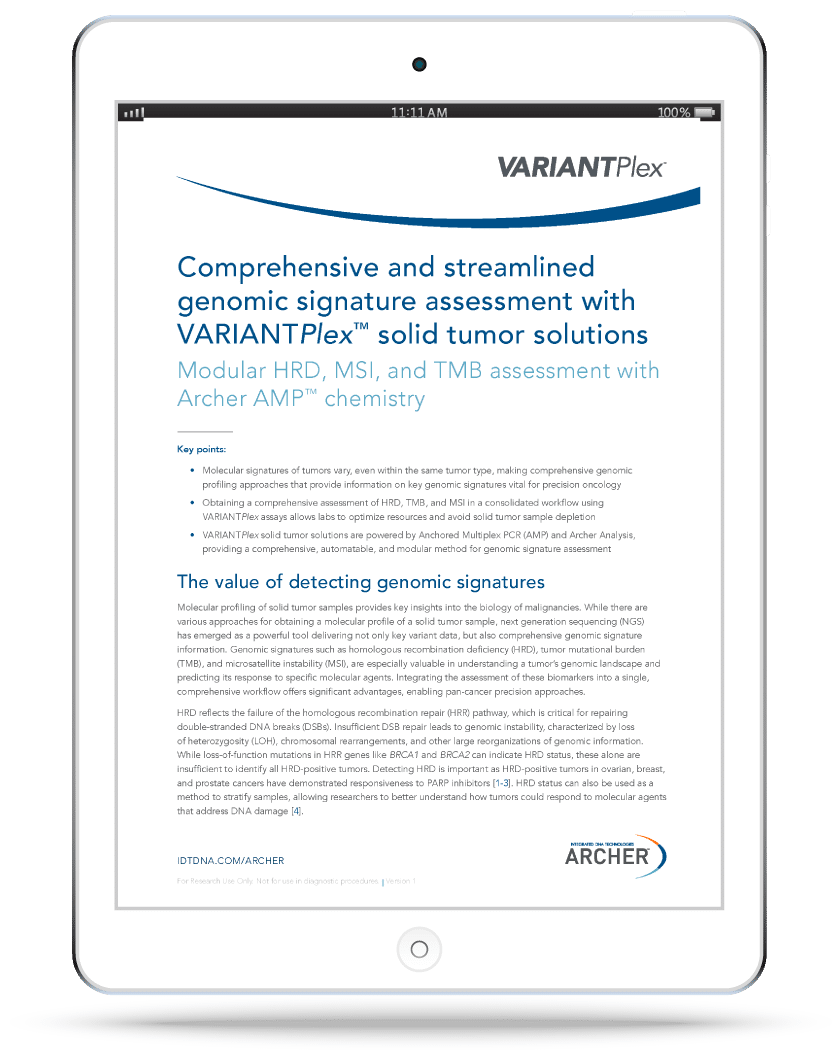

Comprehensive genomic profiling for solid tumors with content-flexible panels and genomic signature modules to optimize use of sequencing resources for your insight needs.

Understand the hidden risks of overlooking comprehensive genomic signature assessments. VARIANTPlex™ solid tumor solutions, powered by Anchored Multiplex PCR (AMP™) and Archer® Analysis, deliver a comprehensive, automatable workflow for high-confidence genomic profiling.